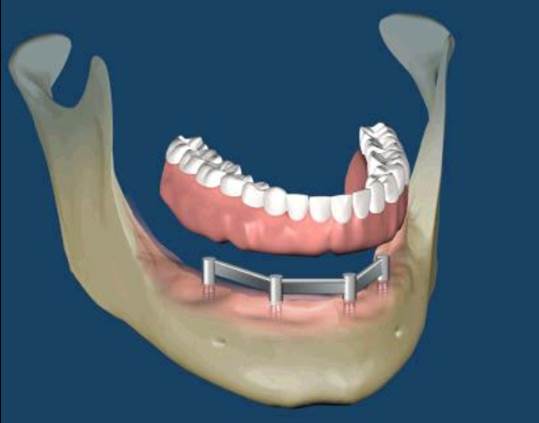

All-on-Fou/Six

近年來由於人工植牙的技術普及,患者大都知道植牙可做固定式假牙,但同樣的有時患者因為身體、經劑因素等受限,也可以考慮植入幾支人工植牙,再完成固定可撤式活動義齒,這樣可讓活動式假牙的固定性有效加強。通常上顎可用6支植體,下顎則4-5支植體固定,如需更穩定的受力,亦可再增加植體數目。(圖52-55)

圖52

圖53

圖54

圖55